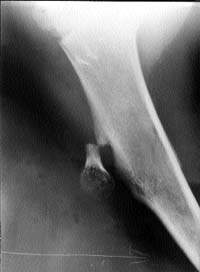

Рентген экзостоза локтевого отростка: медицинские изображения